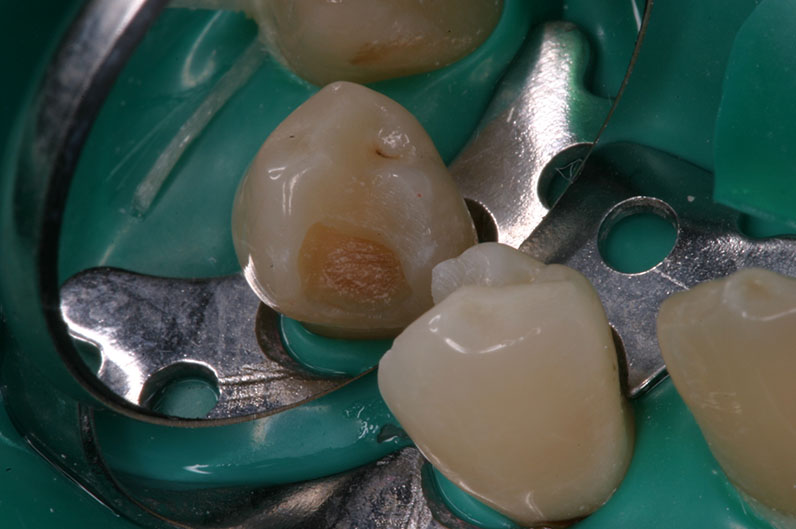

Prima dello scavo

con Facelight